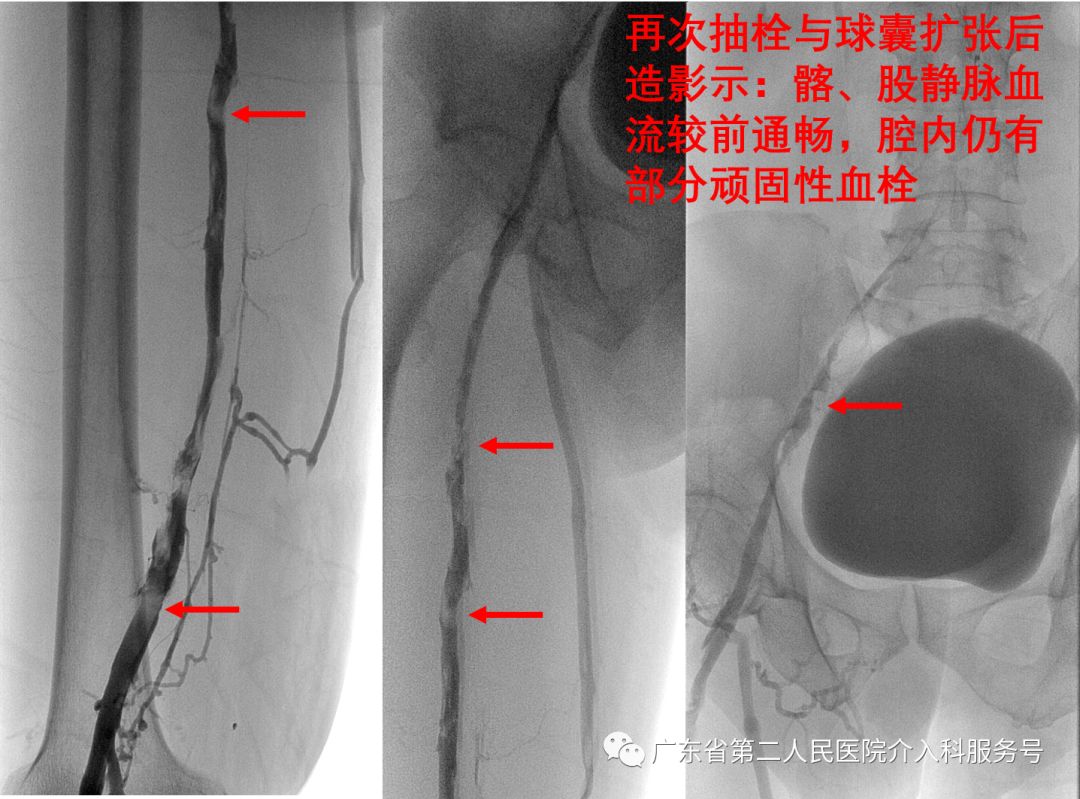

再次抽栓与球囊扩张后再造影显示:髂、股静脉血流较前通畅,腔内仍有部分顽固性血栓残留(如下图),则留置腘静脉导管鞘回病房持续溶栓治疗。